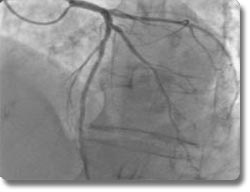

心脏介入诊疗技术(经皮腔内冠脉成形术(PTCA)及支架植入)

PTCA及支架植入术是当今世界上治疗冠心病最先进的方法。在X线透视下,将球囊导管送到病变的冠状动脉,扩张狭窄的血管并植入支架支撑,是内科治愈冠心病最有效的手段。我科1984年开展选择性冠状动脉造影、1994年开展PTCA及支架植入术,现已累计病例2000余例次。接受PTCA及支架植入术的患者最大年龄为92岁。